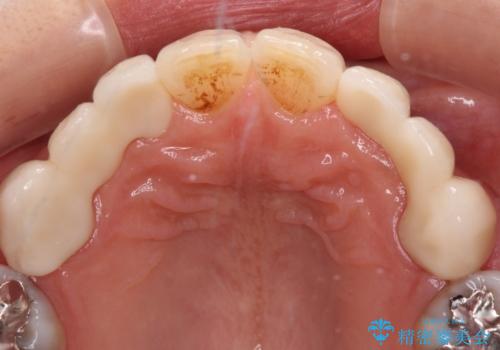

上顎は左右ともに小臼歯が欠損しており、右側は乳前歯が残っている状態でした。

ブリッジによる補綴治療にて、欠損や隙間を補完することとしましたが、神経を取り除いたり、審美的に不自然になることを避けるため、部分矯正を併用することとしました。

乳歯は事前に抜歯することとしました。